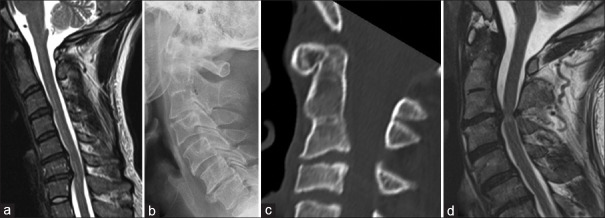

Background: Congenital block vertebrae (BV) is a common condition resulting from segmentation disorders during embryonic development, leading to the fusion of adjacent vertebrae. BV at C2-C3 (cervical vertebrae 2nd-3rd) level is the most common segmentation anomaly. Labeling this correctly is the requirement for exact labeling of the spine. Diagnosing BV may not be challenging; however, differentiating BV from the long C2 can be tricky. Our study proposes a novel method of recognizing BV by measuring their height to aid in accurately distinguishing BV from normal vertebrae.

Methods: This retrospective study compared C2 vertebral heights between two groups: 50 patients with normal cervical spine magnetic resonance imaging (MRI) and 30 patients with congenital fusion at the C2-C3 levels. Using T2-weighted midsagittal MRI images, the height of the C2 vertebra was measured from the tip of the odontoid process to the posteroinferior part of the vertebra. Data analysis was performed using independent t-tests to evaluate the differences in measurements.

Results: The mean C2 vertebral height for the normal cervical spine group was 33.22 mm, while the congenital fusion group exhibited a significantly higher mean height of 45.59 mm. These findings were statistically significant, indicating that a C2 vertebral height exceeding 33 mm is atypical in normal individuals. Our proposed threshold measurement aids in distinguishing between single vertebrae and BV.